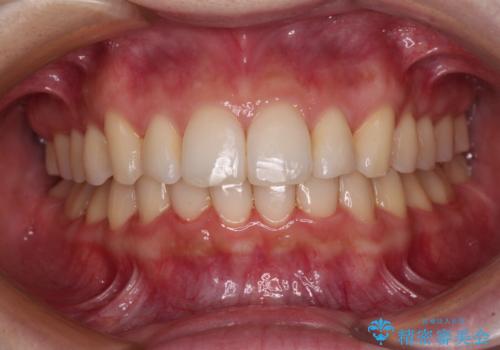

気になる前歯を治したい 短期間でのインビザライン矯正

担当医 藤巻太一朗